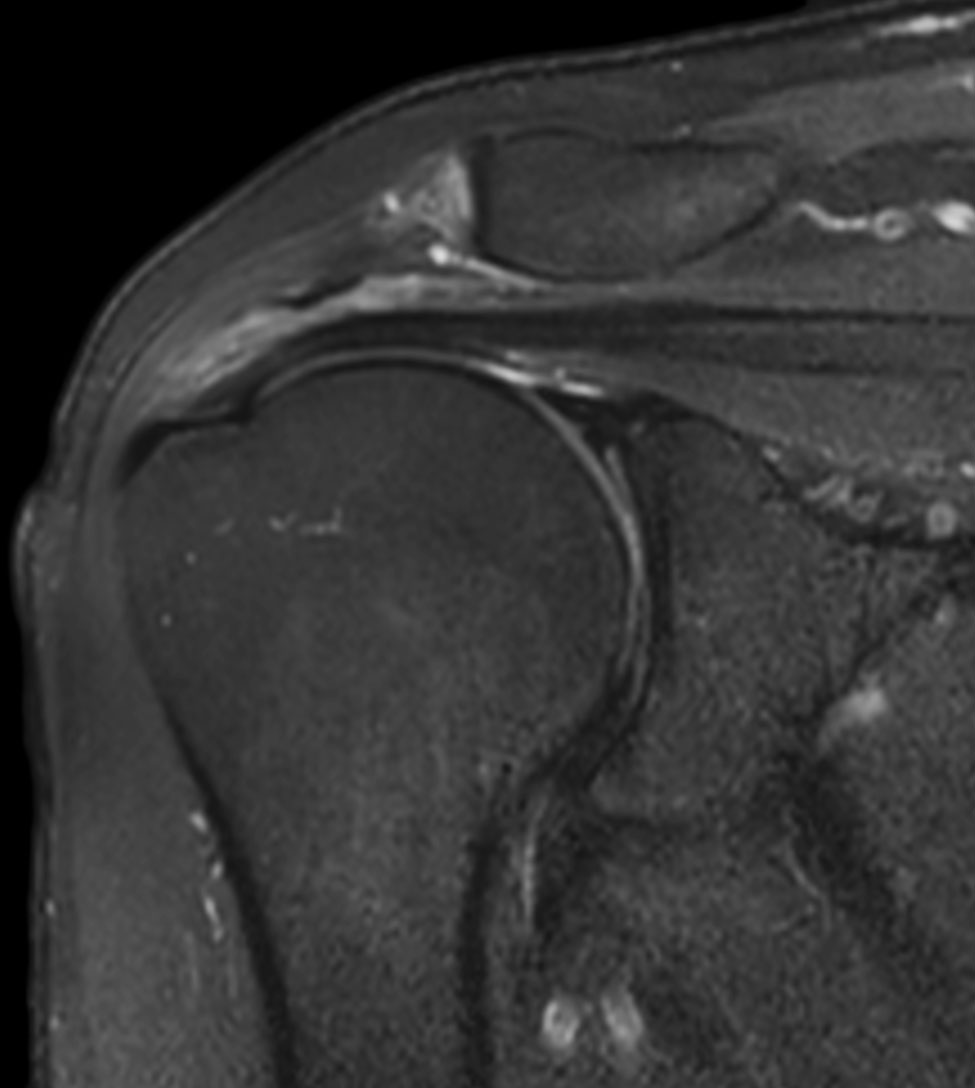

Shoulder imaging using ComforTone